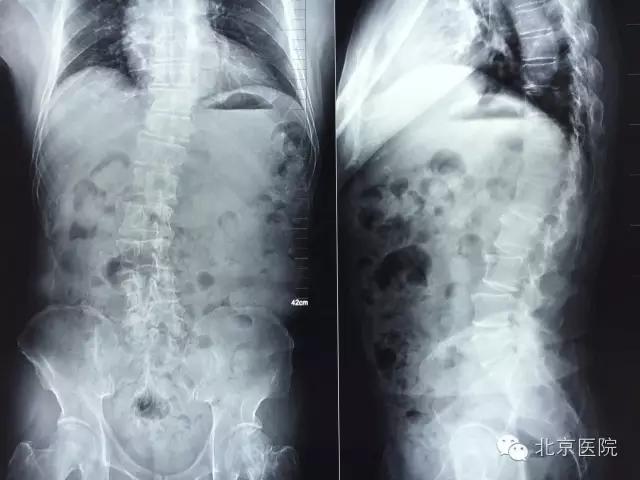

近日,北京医院骨科成功治疗一名合并小儿麻痹症的脊柱侧弯患者。患者陈某某,男,62岁。年幼时因小儿麻痹症导致左下肢无力,主要靠右下肢行走。随着年纪增大,出现脊柱侧弯、腰疼,近年来腰疼逐渐加重伴右下肢放射痛,间歇性跛行小于100米,右下肢无法完成既往行走功能。到当地医院就诊,经针灸、理疗、药物等多种方法对症治疗无法缓解,后到北京医院骨科就诊。

患者由张啟维副主任医师接诊。他根据病情及临床资料诊断考虑患者属于小儿麻痹症后遗症导致的脊柱侧弯,随着年龄增大,脊柱侧弯发生退变并加重,导致椎管狭窄。椎管狭窄压迫神经导致患者出现腰疼及右下肢神经肌肉功能障碍。而患者由于小儿麻痹导致左下肢长期无力,如果其右下肢再出现神经肌肉功能障碍,今后将面临双下肢瘫痪,永远不能行走、坐轮椅的风险,手术治疗很必要。但患者合并糖尿病、高血压等内科疾病。既往有骨质疏松症导致的股骨颈骨折病史,病情比较复杂,客观上讲,麻醉及手术的风险较大。如手术过程出现意外,患者极有可能面临瘫痪的危险。因此,此手术极具挑战。

入院后,骨科闵楠医生带领住院医师团队积极完善各项检查,对患者进行术前安全评估及准备。张啟维副主任医师对患者进行了认真而仔细的查体,并结合病人症状及影像学资料为患者制定了一套安全有效的治疗方案。在方案制定过程中,张啟维副主任医师既考虑到充分减压以解除患者术前神经压迫症状,又考虑到对患者侧弯进行有效矫形以恢复脊柱力线平衡。同时,还要结合患者合并多种内科疾病、身体条件较差的实际情况,尽量在保证效果的前提下将手术小型化、微创化,以降低手术及麻醉给患者带来的创伤,进而降低手术麻醉风险。张啟维副主任医师结合自己出国学习所获得的先进技术,根据实际病情为患者制定了最适合的微创切开手术方案:即后柱截骨(PCO Posteiror Column Osteotomy)矫形联合腰椎4-5椎间融合加后路固定融合术。PCO后柱截骨术手术保留了椎板、棘突,既减少了手术神经、硬膜的损伤及出血,又为后柱植骨融合准备了良好的植骨床,也减少了临近节段退变几率,成为治疗侧弯畸形切开手术微创化的重要术式。是目前国际脊柱畸形手术微创化发展的重要成就之一。